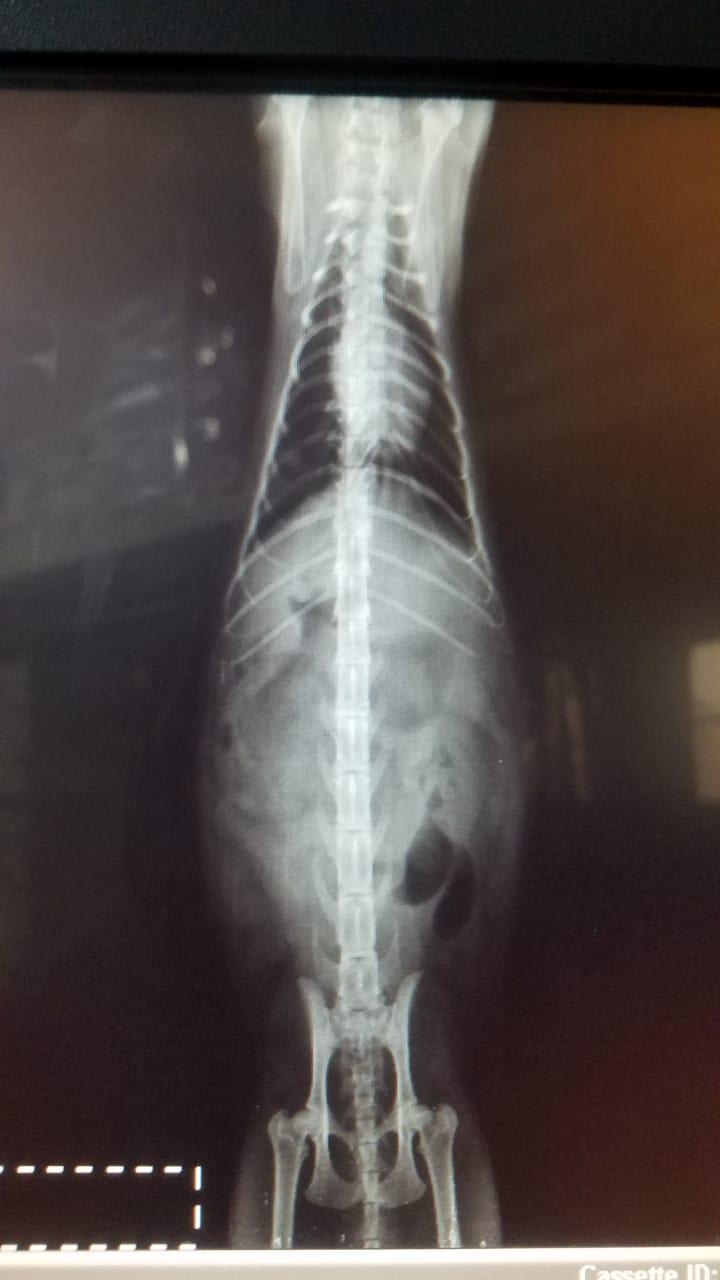

My cat wasn’t feeling well, he was throwing up and had sever fever, 105.2. I took him to the vet, we got all his tests done, and the xrays,but couldn’t figure out the reason. Vet put him on IV fluid for three days, but my cat still isn’t eating by his own and is lethargic. Please help me if you know what could be the reason or how can I make him eat.

I am so sorry to hear that Oreo is not doing well. His x-rays look like he has some dilated bowel, which could indicated his intestines aren't moving well or he may be have an obstruction in his intestines. I would recommend taking him back to your vet. You may need to repeat the x-rays or an ultrasound to see if his intestines have changed in appearance or not and likely need more fluid treatment to keep Oreo hydrated. Fluids also can help to reduce the fever. Some cats with fevers like that and problems in their digestive tract, need surgery to either try to remove an obstruction or take biopsies to get a diagnosis of what is going on. Your vet also may have appetite stimulant, anti-nausea medication, and even fever reducers that may make Oreo feel better. I hope Oreo gets the treatment he needs to get back on track very soon. Good luck!